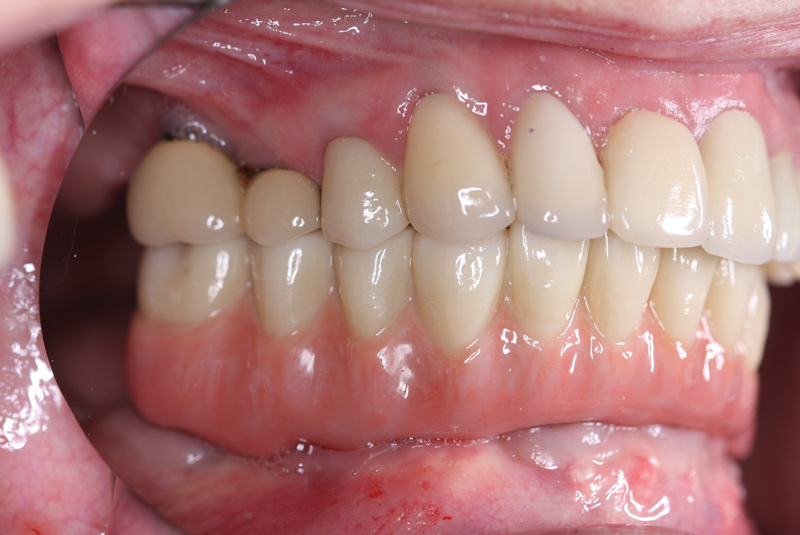

Fig 21. Postoperative close-up retracted facial view and right lateral view of the patient with her full zirconia implant-supported restoration that was salvaged using the fixed locator system.

Figure 21

Fig 22. Postoperative close-up retracted facial view and right lateral view of the patient with her full zirconia implant-supported restoration that was salvaged using the fixed locator system.

Figure 22

Delivering the Salvaged Full Zirconia Prosthesis

The retrofitted and salvaged full zirconia prosthesis was then reseated; proper and full seating of the green retentive ball was confirmed by an audible clicking sound. The prosthesis was then secured to the screw-retained abutments. The screw access holes were then sealed using polytetrafluoroethylene tape and either pink (eg, in gingival areas) or tooth-colored (eg, premolar area) acrylic material (Figure 21 and Figure 22). Considering the patient's aggressive grinding habit, her occlusal night guard was adjusted to ensure a correct fit to the new prosthesis.